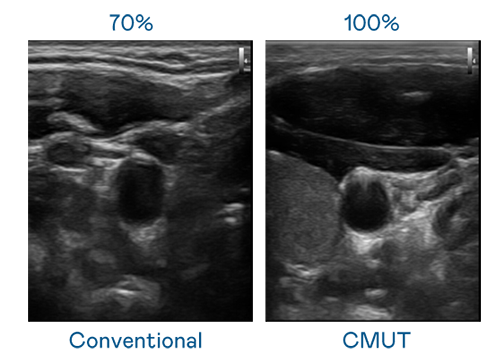

CMUT 技术是一种用电容式微机电元件来产生超音波讯号的技术。与传统 PZT 压电式技术相比,CMUT 频宽增加 30%,更宽频的超音波讯号让影像解析度大幅提升,是实现高影像品质医疗超音波扫描、促进精准医疗发展的关键技术。

大频宽带来超清晰影像

超音波影像的解析度高低,首先取决于探头能发出的讯号频宽。9001cc 以诚为本 CMUT 可提供高清晰的超音波讯号,提供高频宽、高灵敏度、影像纹理细节更高的超音波影像,协助医护人员缩短影像判读时间及利用精准的医疗影像进行诊断。